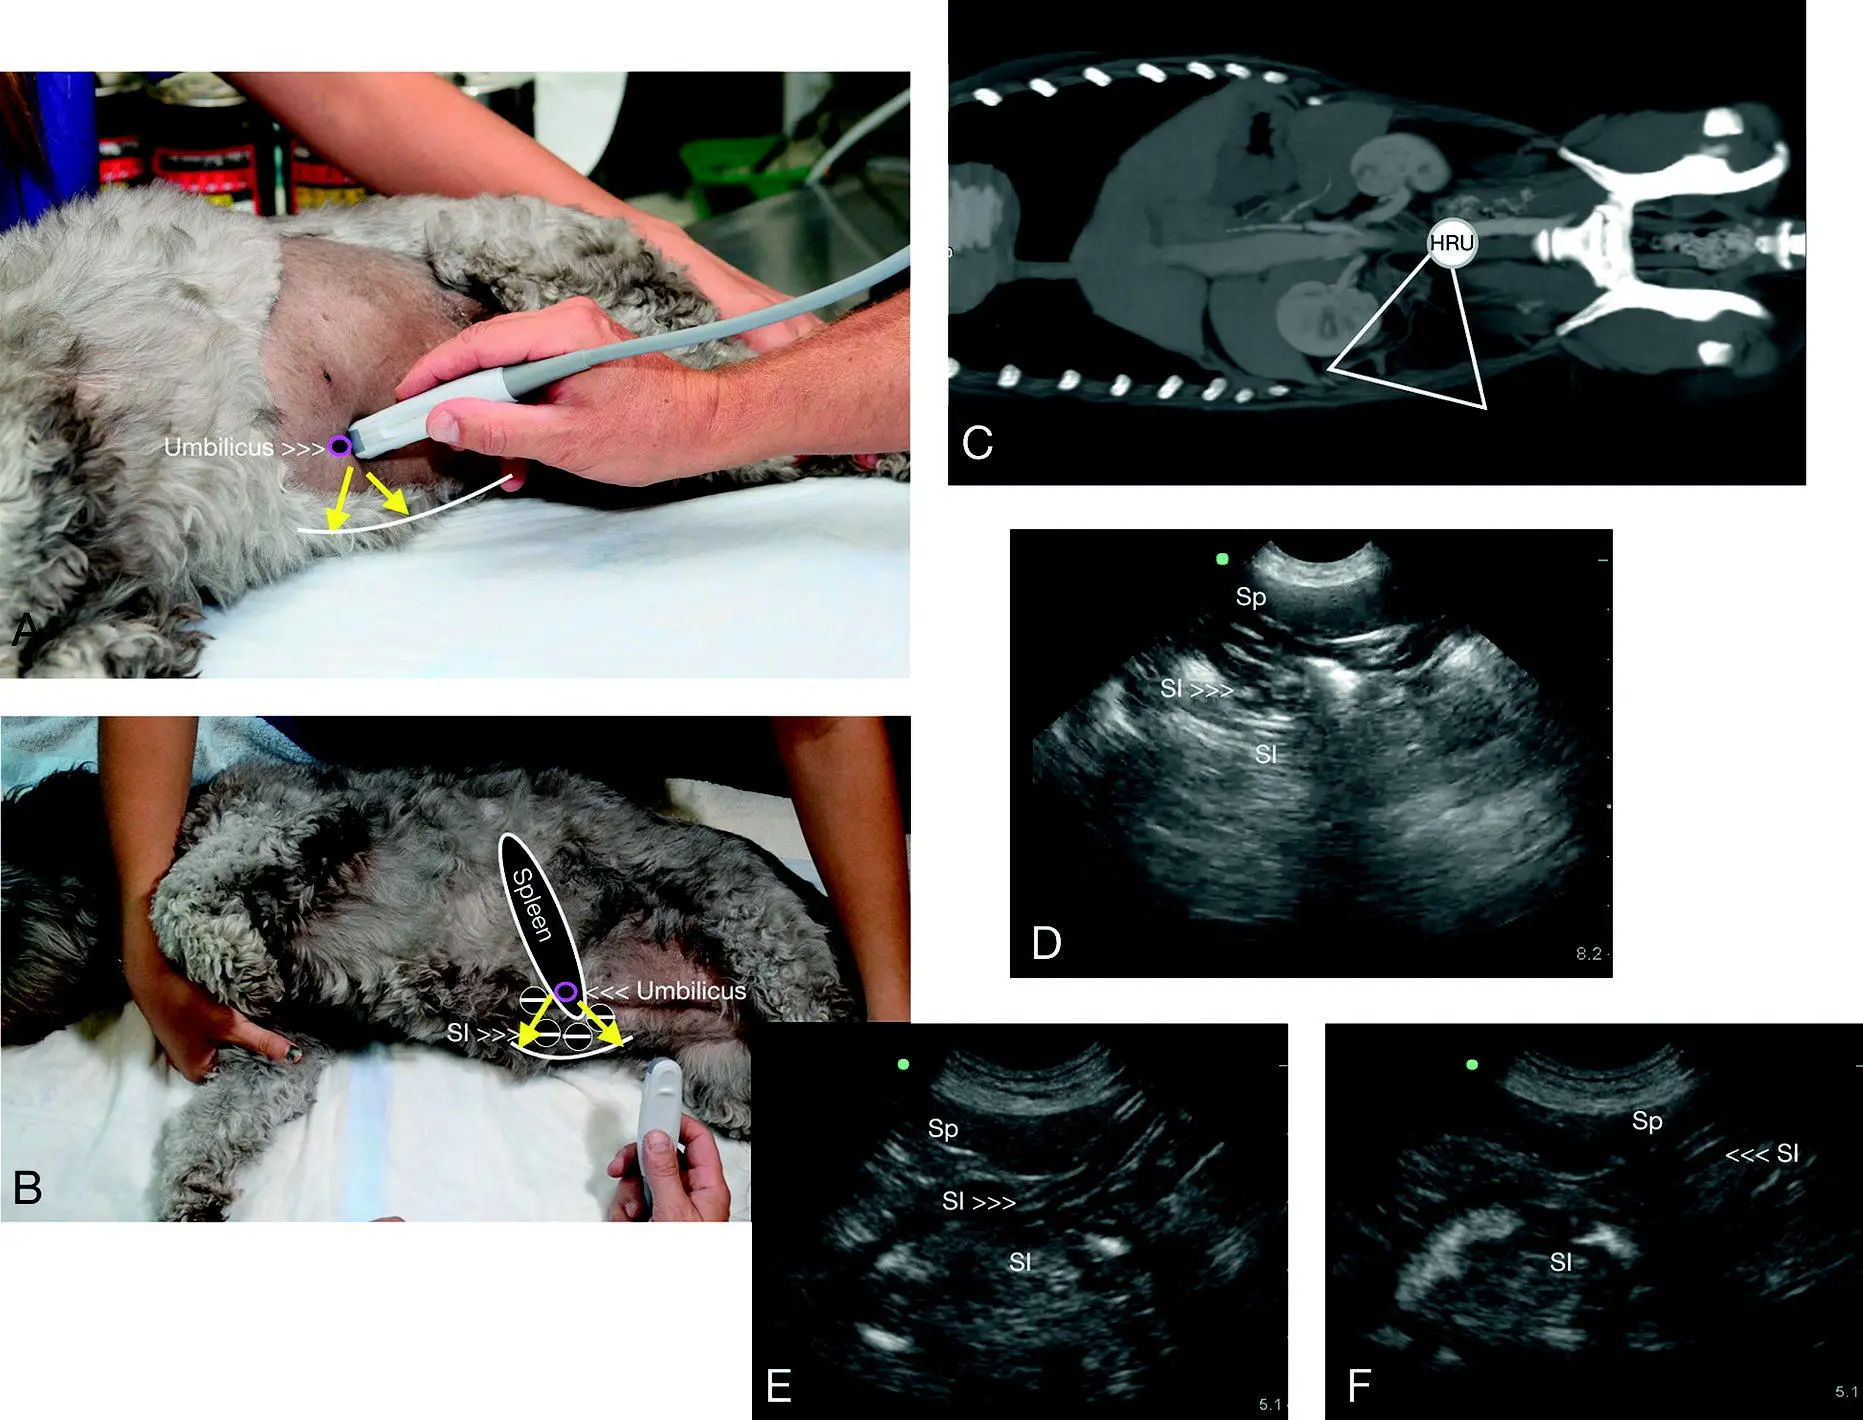

Figure 6.27. Calculi versus intestinal tract. The sonographer will readily appreciate deviations from the expected appearance of the urinary bladder at the CC view. In images (A), (C) and (E) bladder calculi are evident by clean shadowing through the far‐field and contained within the lumen of the urinary bladder. Moreover, they should settle at the “CC pouch” where free fluid would pocket being at the CC view's most gravity‐dependent region. In (B), (D) and (F) are examples of air‐filled intestinal tract that mimic urinary bladder calculi illustrating how care should be taken. By examining (and magnifying) more closely, the bladder lumen can be seen to be pushed into the lumen by the loop of intestinal tract as in (B) and (D) indicated by the cursors (V). Moreover, an abdominal radiograph may be added to the diagnostic work‐up.

Source: Reproduced with permission of Dr Gregory Lisciandro, Hill Country Veterinary Specialists and FASTVet.com, Spicewood, TX.